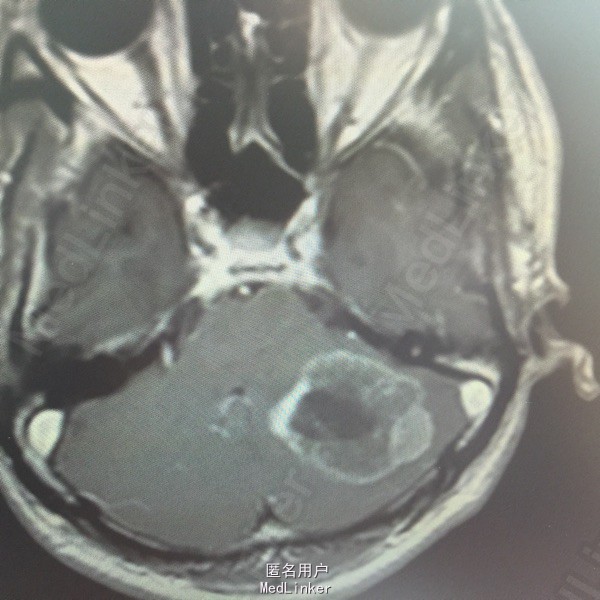

男,54岁,以头痛半个月入院。 现病史:半个月前无诱因头痛,呈胀痛,无呕吐,无意识障碍,病来咳嗽、咳痰,体重减轻约5斤,无发热。 既往史:无特殊。

查体:BP:150/100mmHg,神清语明,两瞳孔等大正圆,直径约3.0mm,光敏,四肢肌力5级,肌张力正常,腱反射艹,左侧共济运动阳性,病理征阳性,脑膜刺激征(-)。 辅查:见下:

肺癌脑转移。 影像解读(影像如何解读是临床工作中非常重要的一环)。 左侧额叶近皮质长Tl长T2信号,局部颅骨缺损,右侧枕叶不规则病灶,TlWl呈中心呈等信号,周围高信号,T2Wl呈高低混杂信号,伴大片水肿,相邻侧脑室后角、胼胝体受压。增强呈不规则环环强化。 已进行局部放疗治疗。